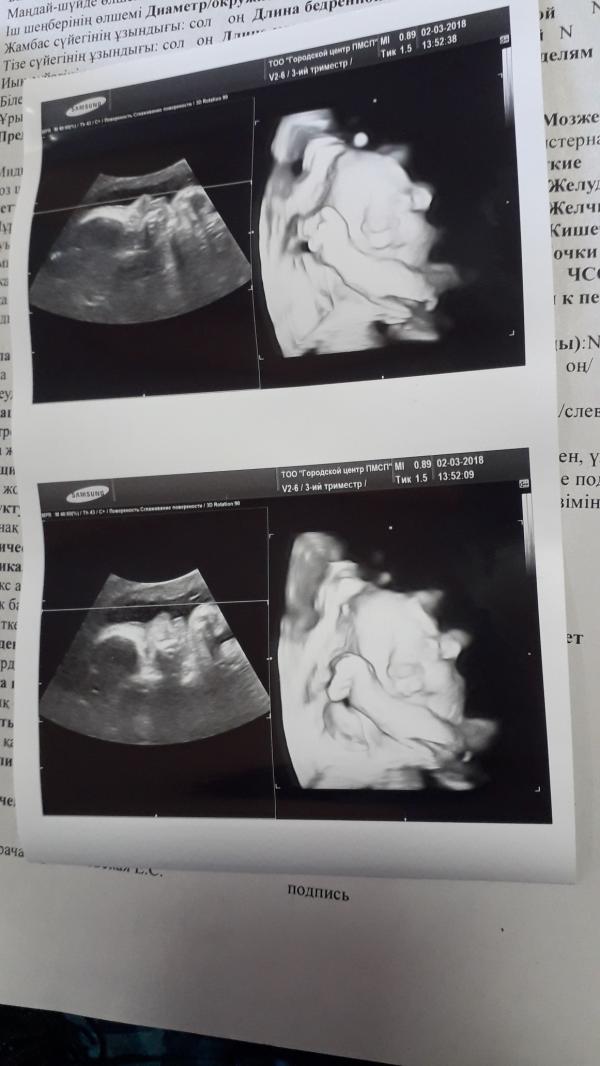

Еще чуть чуть)))И опять папина моська 😄😄😄